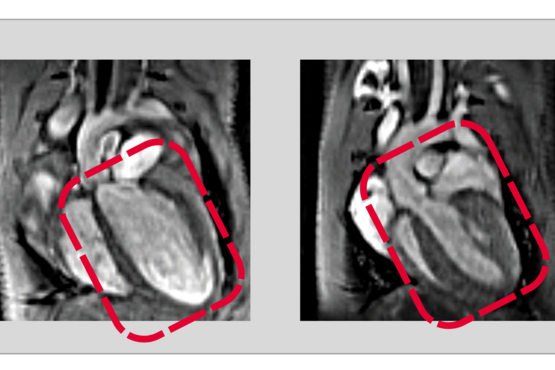

Increasing complexity in the heart: How two related proteins control development of the heart

RBPMS and RBPMS2 regulate cell division and function during heart development